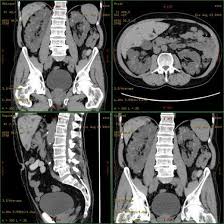

A kidney x ray known as a retrograde pyelography is a test that helps your doctor look at how your urinary system is working and check that the shape and size of your organs are normal. What is a kidney ureter and bladder x ray. What happens after i get a kidney.

They show pictures of your internal tissues bones and organs.

What is a kidney ureter and bladder x ray. A kidney ultrasound is a non invasive way to take images of your right and left kidneys. What happens after i get a kidney. Because they utilize soundwaves rather than radiation to produce images ultrasounds are considered safer to patients and healthcare workers than x rays.